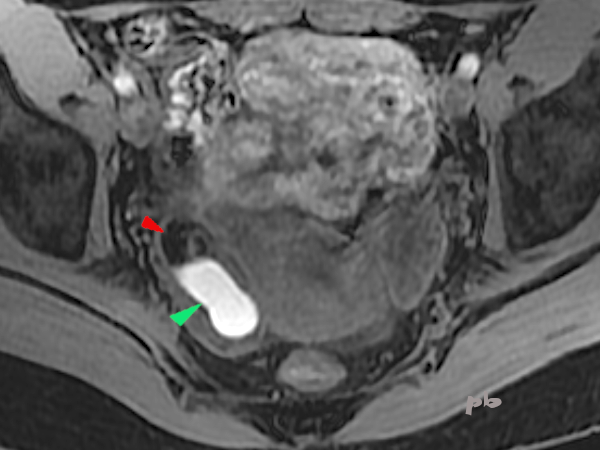

19+20+21- Kystes endométriosique et dermoïde – IRM

Sémiologie IRM comparative entre un kyste endométriosique (►) et un kyste dermoïde (►), tous les 2 ovariens droits. Ovaire gauche porteur d’un follicule dominant (★).

| T2 (image 19) | T1 sans fatsat (image 20) | T1 avec fatsat (image 21) | |

| Endométriome (►) | hypersignal | hypersignal | hypersignal |

| kyste dermoïde (►) | Hypersignal Nodule central hyposignal | Hypersignal Nodule central hyposignal | Hyposignal Nodule central hyposignal |

Le kyste dermoïde contenant de la graisse, il apparait en noir, sur la séquence T1 fatsat (qui supprime le signal de la graisse). Alors que le signal du sang ne se modifie pas. Les autres tissus contenant de la graisse ((sous-cutanés par exemple) deviennent également noirs.

L’hypersignal en T2 du kyste endométriosique n’est pas très fréquent, ni caractéristique, au contraire du »shading ». L’hypersignal en T1 fatsat permet le diagnostic.

21 – T1 avec fatsat